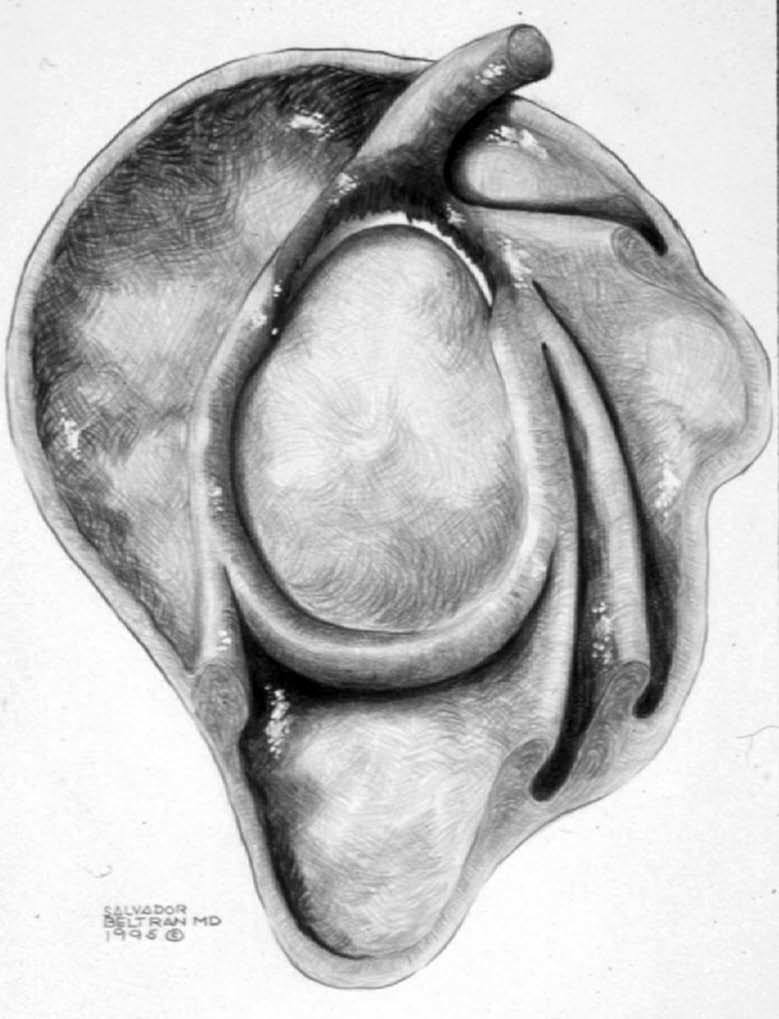

ALPSA (anterior labroliamentous periosteal avulsion)

Al igual que en el apartado anterior, existe también una separación de LG junto con la cápsula y el periostio, pero a diferencia de las lesiones de Bankart o Perthes, el LG se desplaza hacia dentro, por detrás del borde de la glenoides18 (fig. 12). La lesión de ALPSA puede cicatrizar por sinovialización (fig. 12), pero continúa siendo de carácter inestable.

Fig. 12.--ALPSA (anterior labroliamentous periosteal avulsion) agudo (A) y crónico (B). Nótese la separación del labio glenoideo y su desplazamiento posterior y medial por detrás del reborde glenoideo (flecha en A). En una fase crónica el labio glenoideo no se distingue como una estructura separada, sino como un engrosamiento de la unión entre el labio, la cápsula y el periostio (flecha en B).